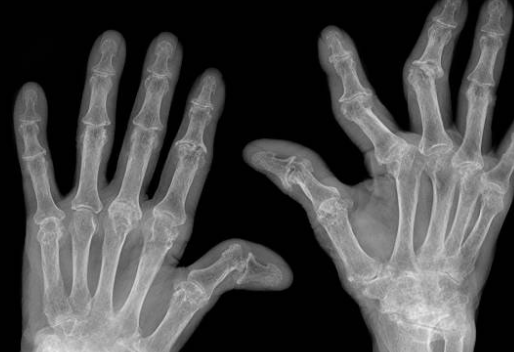

- 류머토이드 관절염: 류머토이드 관절염은 자체면역 반응이 원인으로 발생하는 만성적인 관절염으로, 주로 손과 발의 소근육 및 대형 관절에 영향을 미칩니다. 손과 발의 작은 관절부터 충격을 받는 관절까지 다양한 관절에 염증이 발생하여 관절 통증, 부종, 관절 운동 제한 등의 증상이 나타납니다.

- 관절 부종: 염증이 발생하면 관절 주위에 부종이 생길 수 있습니다. 부종은 관절의 두꺼운 감쇄와 압통을 유발할 수 있습니다.

- 관절 강직성: 관절이 뻣뻣하게 느껴지고 움켜잡거나 움켜매는 능력이 감소할 수 있습니다. 특히 아침에 일어나면 관절의 강직성이 더 심할 수 있습니다.